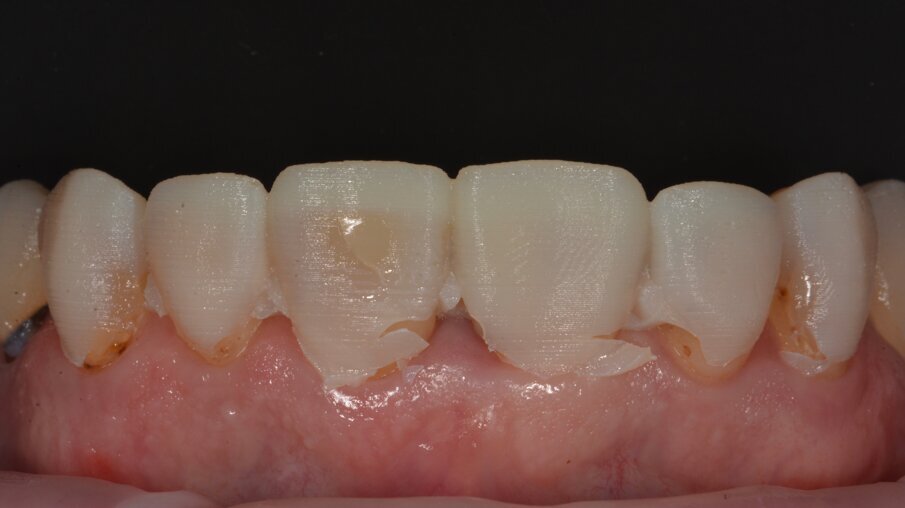

Vooraanzicht van het bovenfront: veel oude vullingen zijn aan vervanging toe door slechte randaanpassing en/of verkeerde kleuren.

Resultaat na verwijderen van alle oude composieten en minimale buccale wegname. De vulling op tand 21 werd behouden omdat deze de week ervoor pas werd geplaatst.

Het intermediair resultaat na opvullen van de buccale vlakken. Voor het afwerken en polijsten werd gebruik gemaakt van het Essential Shape protocol ontworpen door Style Italiano.

Eindresultaat.

Hoogglans kan perfect bereikt worden. Een mooi emergence profiel kan worden gezien.